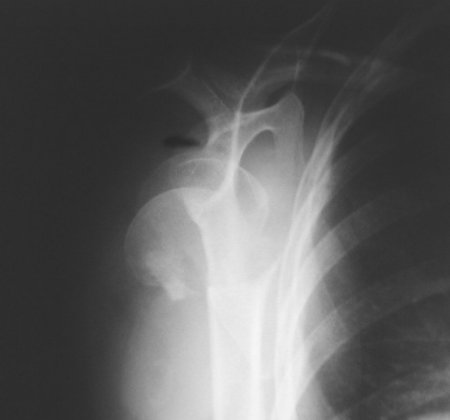

SHOULDER JOINT

Shoulder X-ray